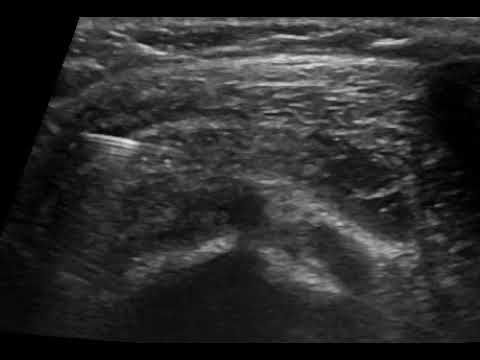

Η καθοδήγηση του υπερήχου εγγυάται τη σωστή και ασφαλή τοποθέτηση του κορτικοστεροειδούς εντός του θυλάκου, αποφεύγοντας την πιθανή έγχυση στον τένοντα, η οποία μπορεί να προκαλέσει φθορά του.

Σε συνδυασμό με την αντιφλεγμονώδη δράση του κορτικοστεροειδούς, η υπερηχογραφική καθοδήγηση παρέχει τη δυνατότητα υδροδιάτασης του θυλάκου πριν την έγχυση του κορτικοστεροειδούς. Η υδροδιάταση περιλαμβάνει έγχυση φυσιολογικού ορού και τοπικού αναισθητικού προκειμένου να εξουδετερωθούν οι συμφύσεις εντός του θυλάκου.